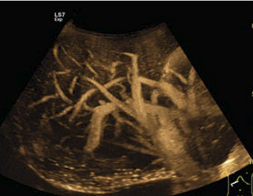

What modality is used in this image?

B-flow